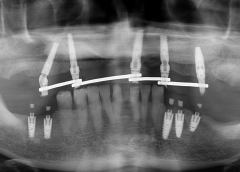

• Tình trạng mất răng:Mất răng R12 đến R27. Mất răng R32, R33, R35, R36. Nhiều răng bị sâu và có những miếng trám lớn.

• Phương hướng điều trị:Phục hồi toàn bộ răng mất bằng 10 trụ Implant và bọc lại răng sứ từ răng số 13 đến số 17.

• Trụ Imlant sử dụng:Implant Mis C1 Đức

• Cấy ghép 10 trụ implant Mis C1 Đức cho toàn hàm

• Phục hình răng sứ Cercon HT